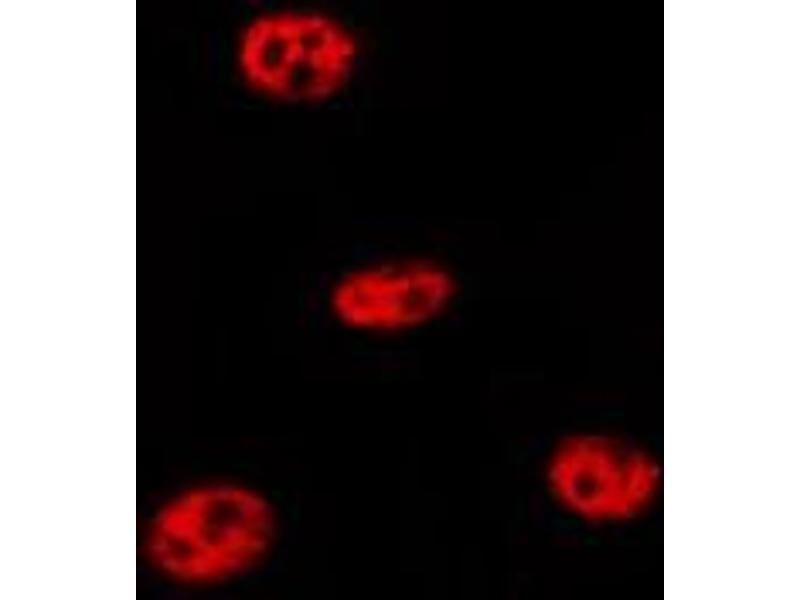

TP53 Reaktivität: Human WB, IHC, ELISA, IF Wirt: Kaninchen Polyclonal unconjugated

Produktnummer ABIN7138434